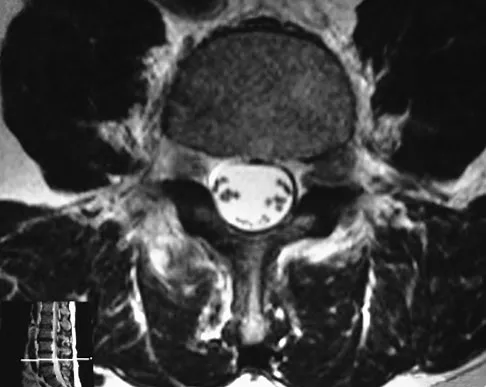

Question 37

Figure 33 shows the MRI scan of a 55-year-old woman who has had a 6-week history of back and leg pain. Which of the following clinical scenarios is most consistent with the MRI scan findings at L4-L5?

Explanation